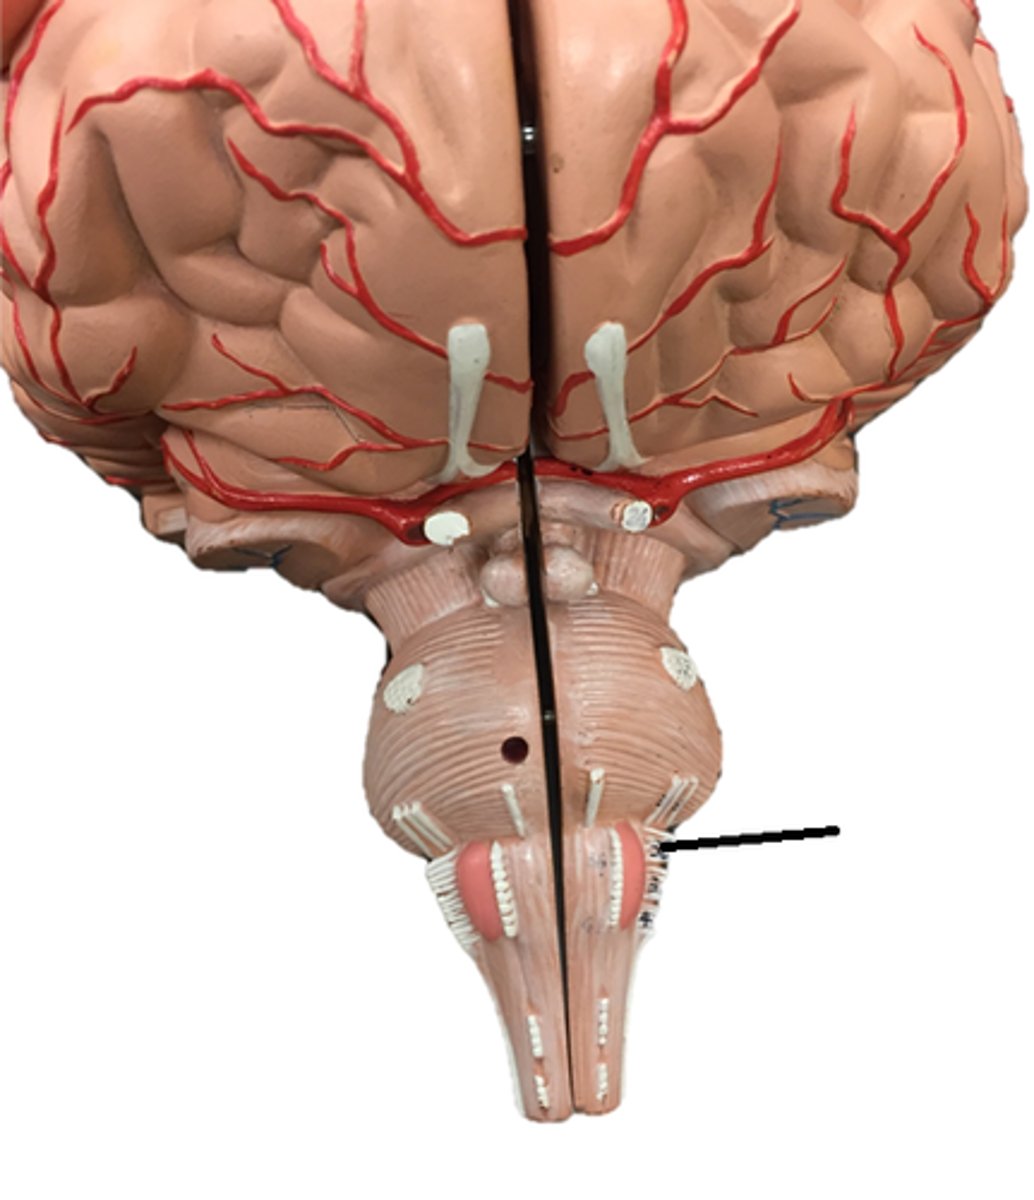

medulla oblongata

pons

midbrain

olive

vermis